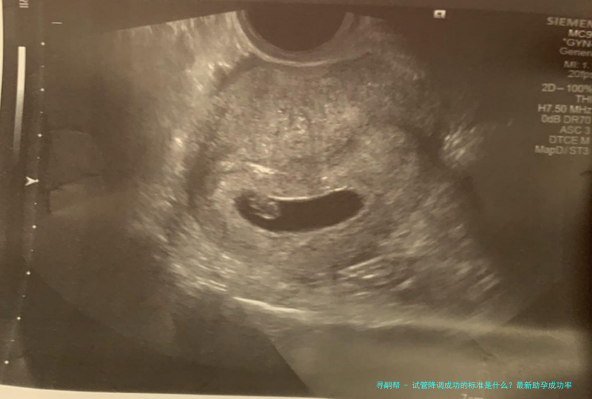

3、B超检查结果

通过B超监测卵巢大小及卵泡成长情形亦是评介降调成效的首要手段其中之一。成功的降调后,可以看到卵巢容积减小,且基础卵泡量数减少或简直消失,说明卵巢活动已得到有效遏止。